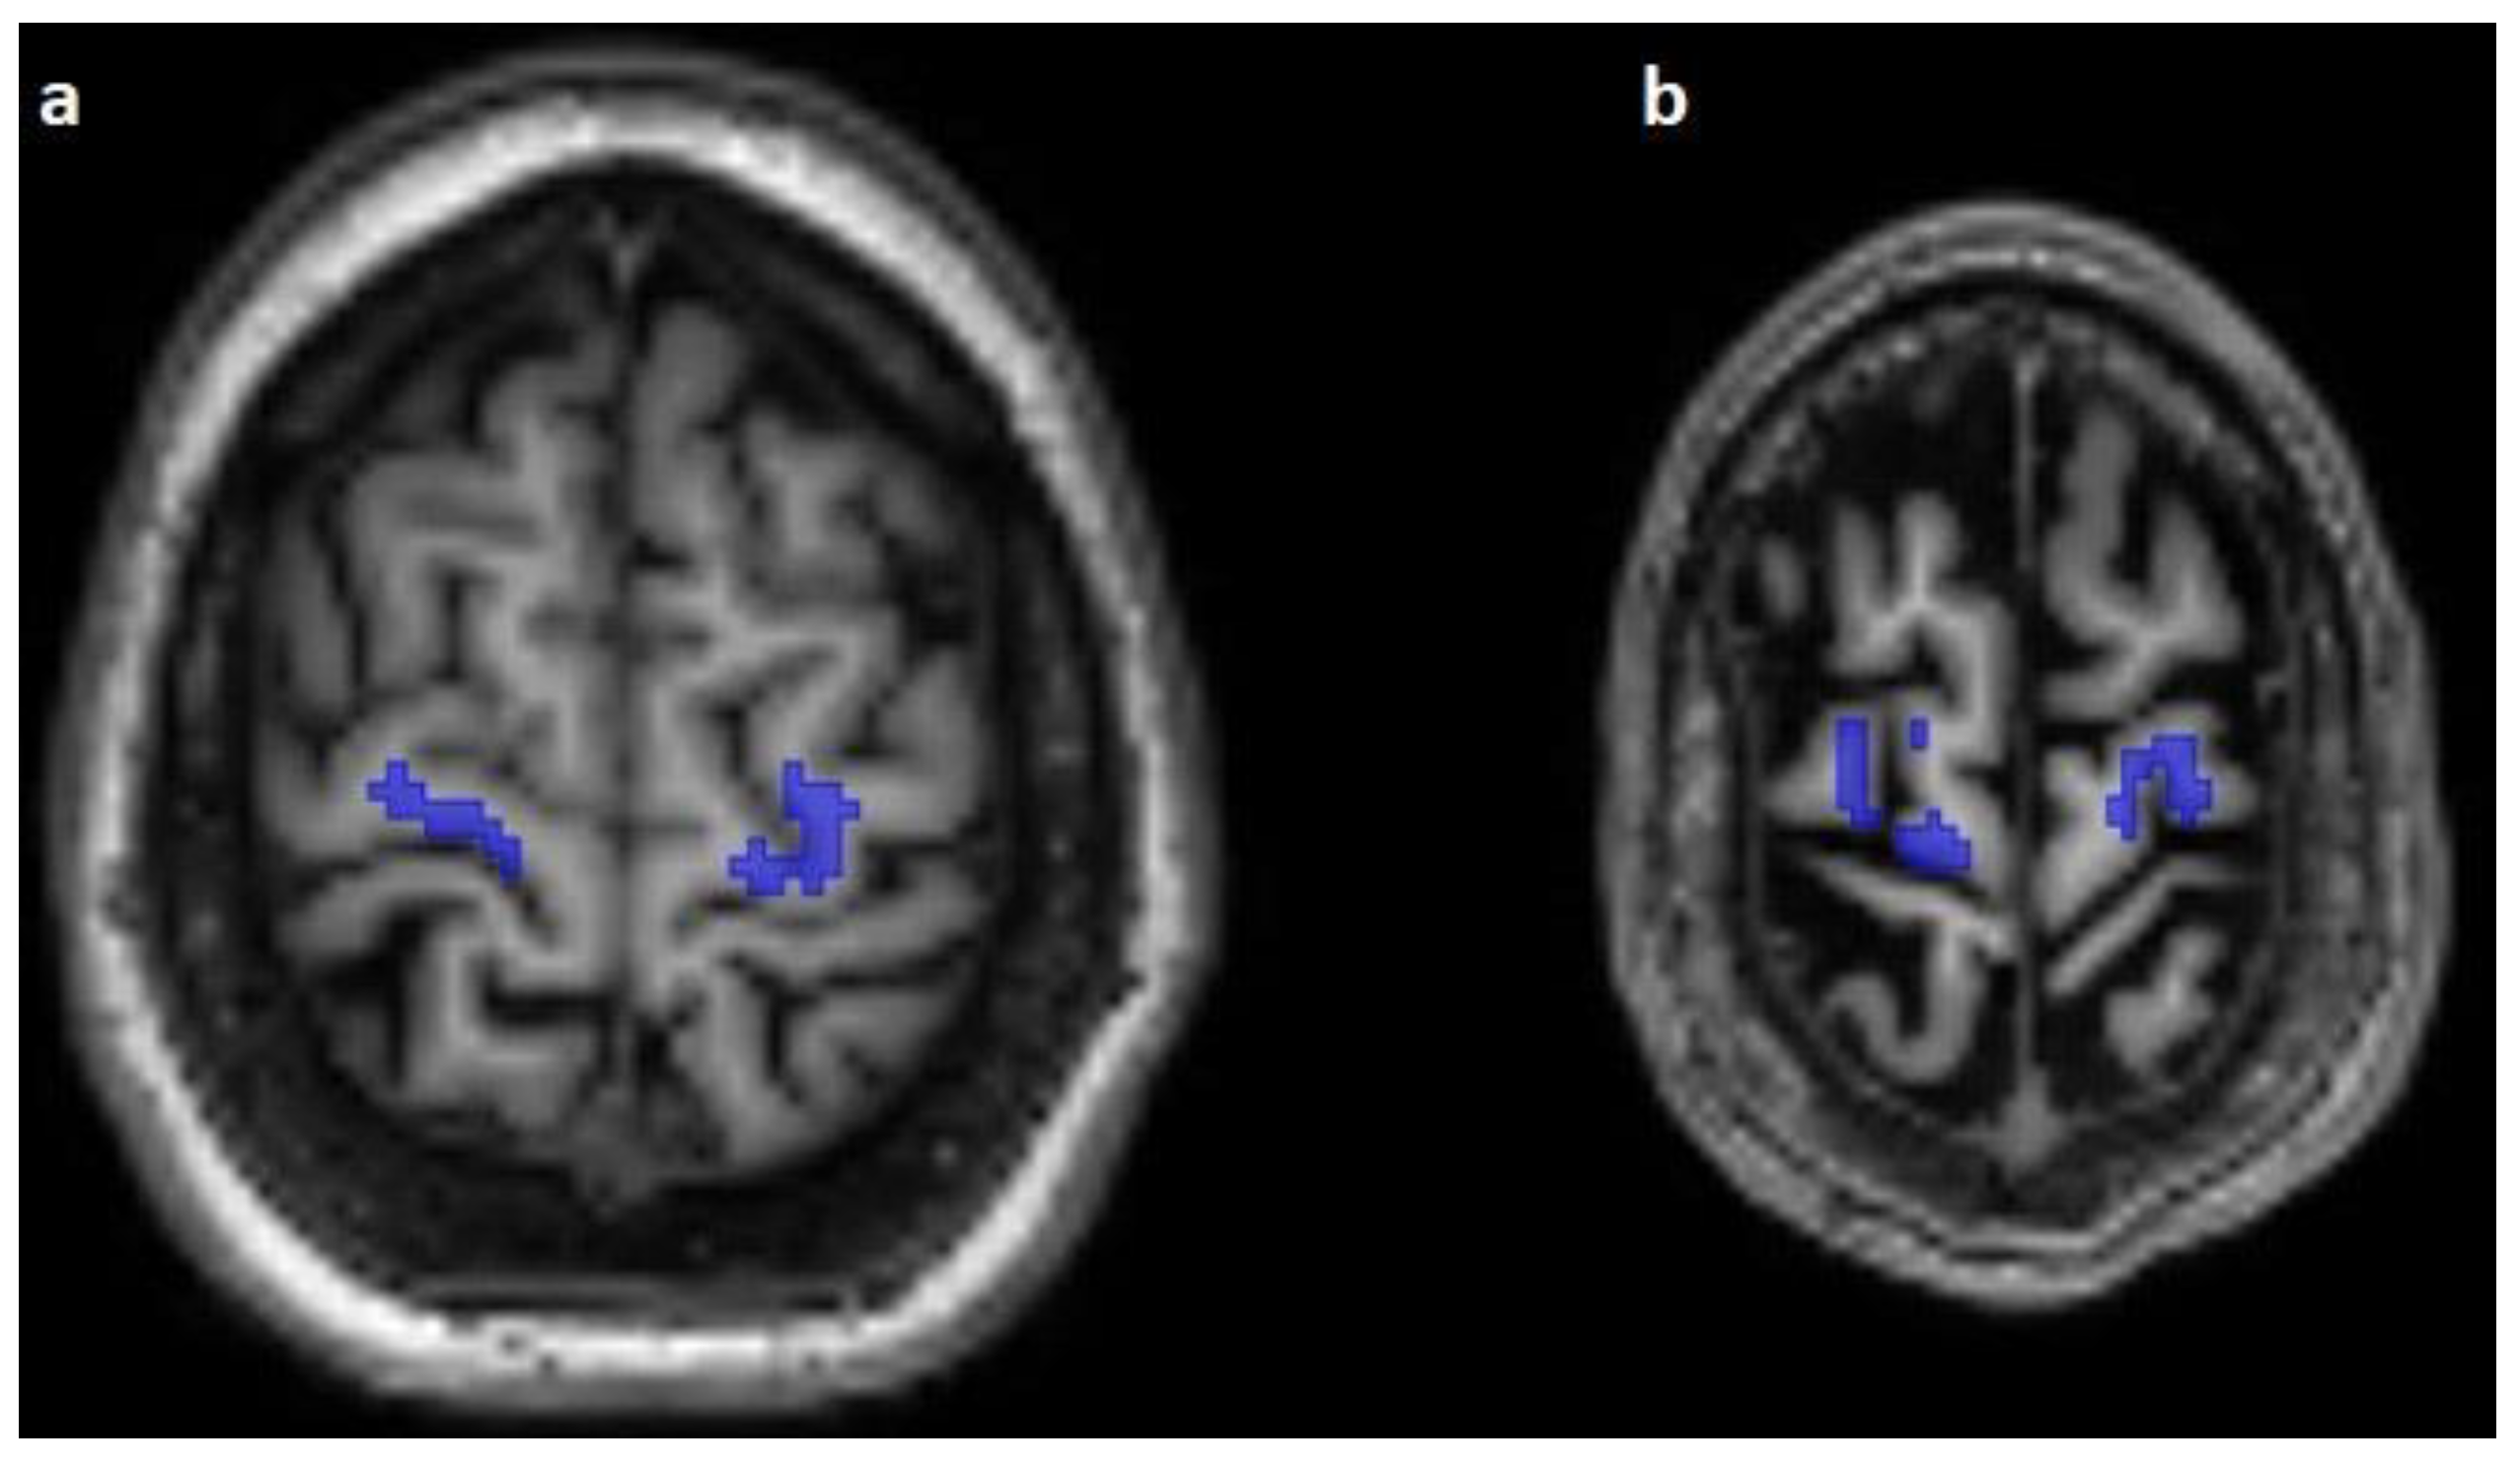

The corticospinal tract traversed the ventral part of the pons in 100/100 cases (100%), traversed the middle-third of the crus cerebri of the mesencephalon in 100/100 cases (100%), traversed the posterior limb of the internal capsule in 100/100 cases (100%), and originated from the medial part of the precentral gyrus in 89/100 cases (89%) (Figure 1, Figure 2 and Figure 3).

Figure 3.

The predicted course of the corticospinal pathway (blue) in the subcortical white matter of the precentral gyrus on axial T1-weighted images. Note the absence of predicted fibers in the subarachnoidal space as well as the fibers following the pattern of the minor gyri (a,b).

The predicted pathway originated from the centrum semiovale directly under the precentral gyrus in 11/100 (11%) cases; 4 subjects (4/25, 16%) were affected in the Emotion regulation dataset, with 3 on the right side and 1 on the left side, and 7 subjects (7/15, 46.67%) were affected in the interTVA dataset, with 4 on the right side, 1 on the left side, and 2 on both sides.

The predicted course originated from the subarachnoidal space between the minor gyri of the precentral gyrus or between the precentral and postcentral gyrus in 8/100 cases (8%) of 4 datasets, and 3 cases (3/25, 12%) of the Emotion regulation dataset, 2 cases (2/15, 13.33%) of the Forrest Gump dataset, 2 cases (2/25, 8%) of the Beijing Enhanced dataset, and a single case of the Test-Retest dataset (1/10, 10%) were affected by this error of prediction. With regard to the number of subjects with falsely segmented origins, there was no statistically significant difference between the two scanner groups (p = 0.06).